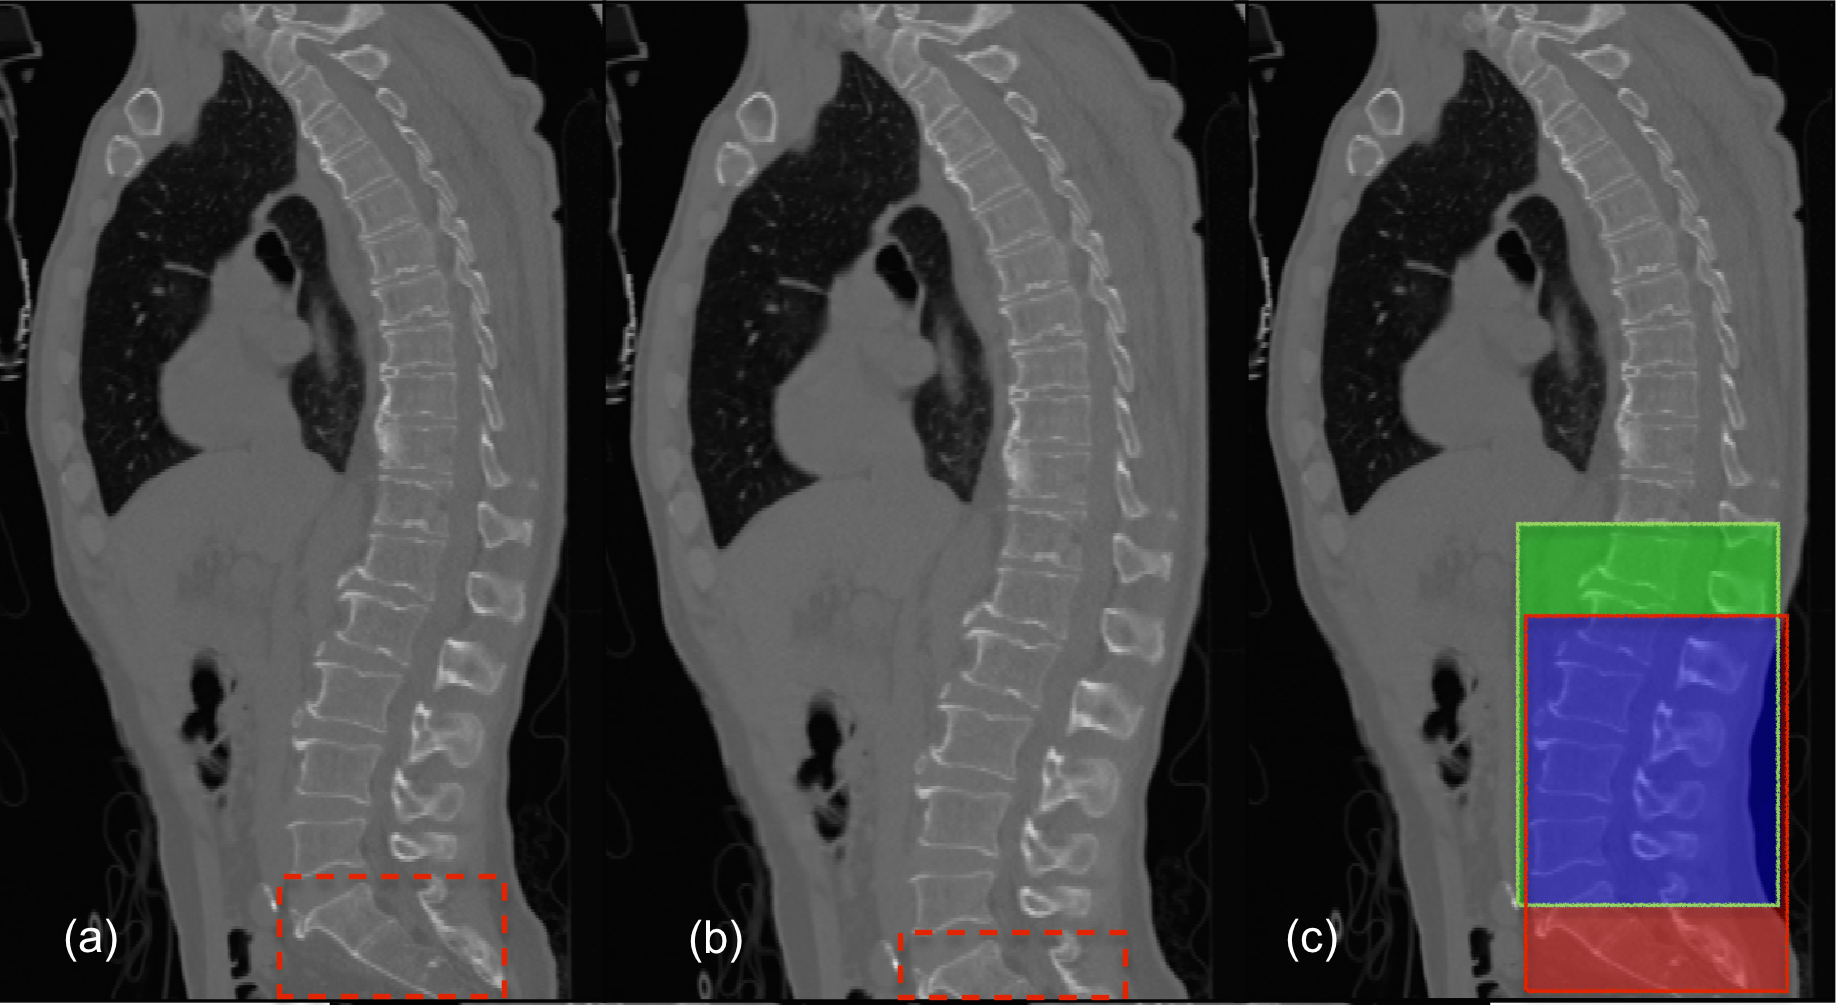

5.2 The Outlier (Case 25 of the xVertSeg Dataset)

As mentioned in section 3 (Lumbar localisation) of the main article, the localisation in Case 25 occurs with a sensitivity of 0.94 (figure 6(c), red outline) as it is the only example in the train and test data that consists of three sacral bones (S1, S2, and S3) within the field-of-view (figure 6(a)). When the scan, with S3 manually cropped off, is used as input (figure 6(b)), the lumbar localisation is perfect (sensitivity of 1.0), as shown by the green outline in figure 6(c). It is clear that the improper localisation is a consequence of working with limited data, and can easily be averted by increasing the variability in the training dataset.